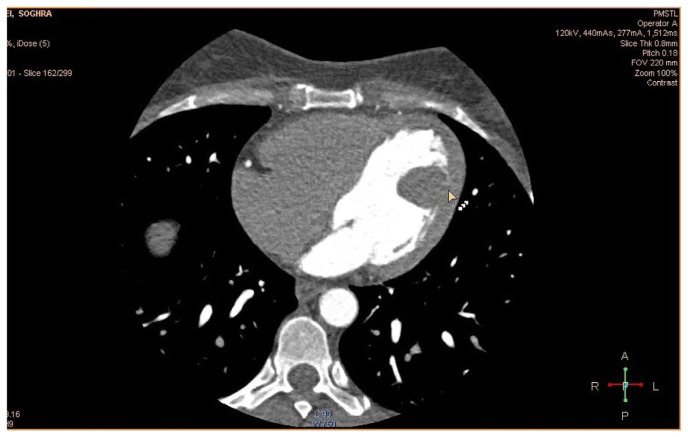

Case presentation: We present a case of a 46-year-old woman with positional vertigo and exertional dyspnea. Transthoracic echocardiography revealed a mobile oval-shaped mass in the left ventricle. Cardiac magnetic resonance imaging suggested a large papillary fibroelastoma. The tumor was successfully resected, and histopathological examination confirmed the diagnosis.